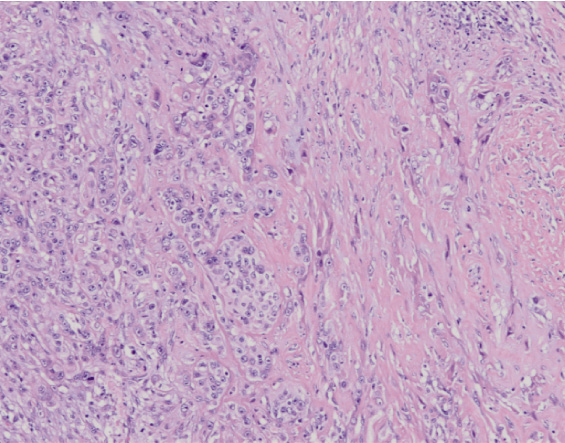

In corso di riunione multidisciplinare, nella quale sono presenti il medico pneumologo (che in questo caso fa parte di una divisione di oncologia toracica), il chirurgo toracico e il radioterapista si discute il caso alla luce dei dati TAC, PET e broncoscopici e si pone indicazione a eseguire mediastinoscopia. Tale procedura ha permesso la campionatura di 5 linfonodi totali, 3 in sede pretracheale destra e 2 in sede paratracheale destra, risultati all’esame istologico sede di metastasi di adenocarcinoma scarsamente differenziato in 4 casi su 5 (Figura 2).

Figura 2. Esame istologico della stazione linfonodale